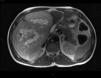

CT scan and MRI showed a mass measuring 20×19.5×13.6cm in length with significant contrast uptake, central necrotic areas and exophytic location (liver segments V and VI), with no infiltration of neighboring organs. The differential diagnosis included hypervascular tumors (adenoma, hypervascular metastasis, sarcoma) (Fig. 1). Gastroscopy and colonoscopy were normal. PET/CT showed no extrahepatic uptake.